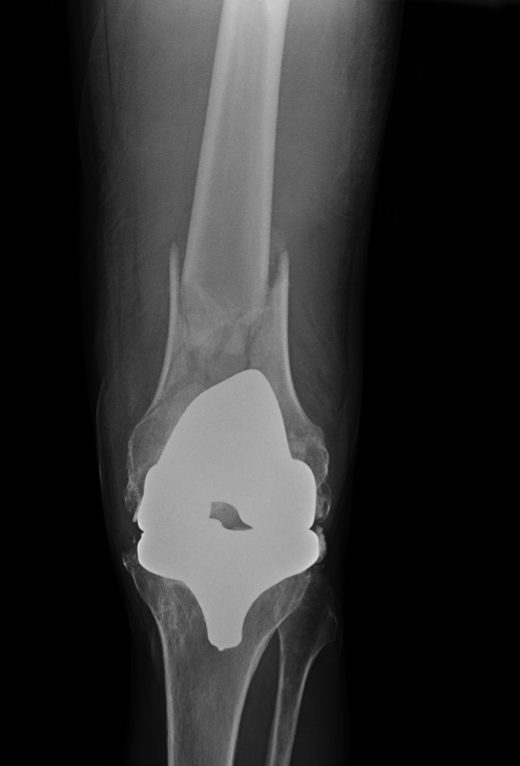

Pijn linker knie na val, wat is de diagnose? Gepost op 23 juni 201723 juni 2017 door netwerkvsseh What’s the Diagnosis? @ emdaily.cooperhealth.org Dit delen: Delen op X (Opent in een nieuw venster) X Share op Facebook (Opent in een nieuw venster) Facebook Delen op LinkedIn (Opent in een nieuw venster) LinkedIn E-mail een link naar een vriend (Opent in een nieuw venster) E-mail Afdrukken (Opent in een nieuw venster) Print Vind-ik-leuk Aan het laden... Gerelateerd